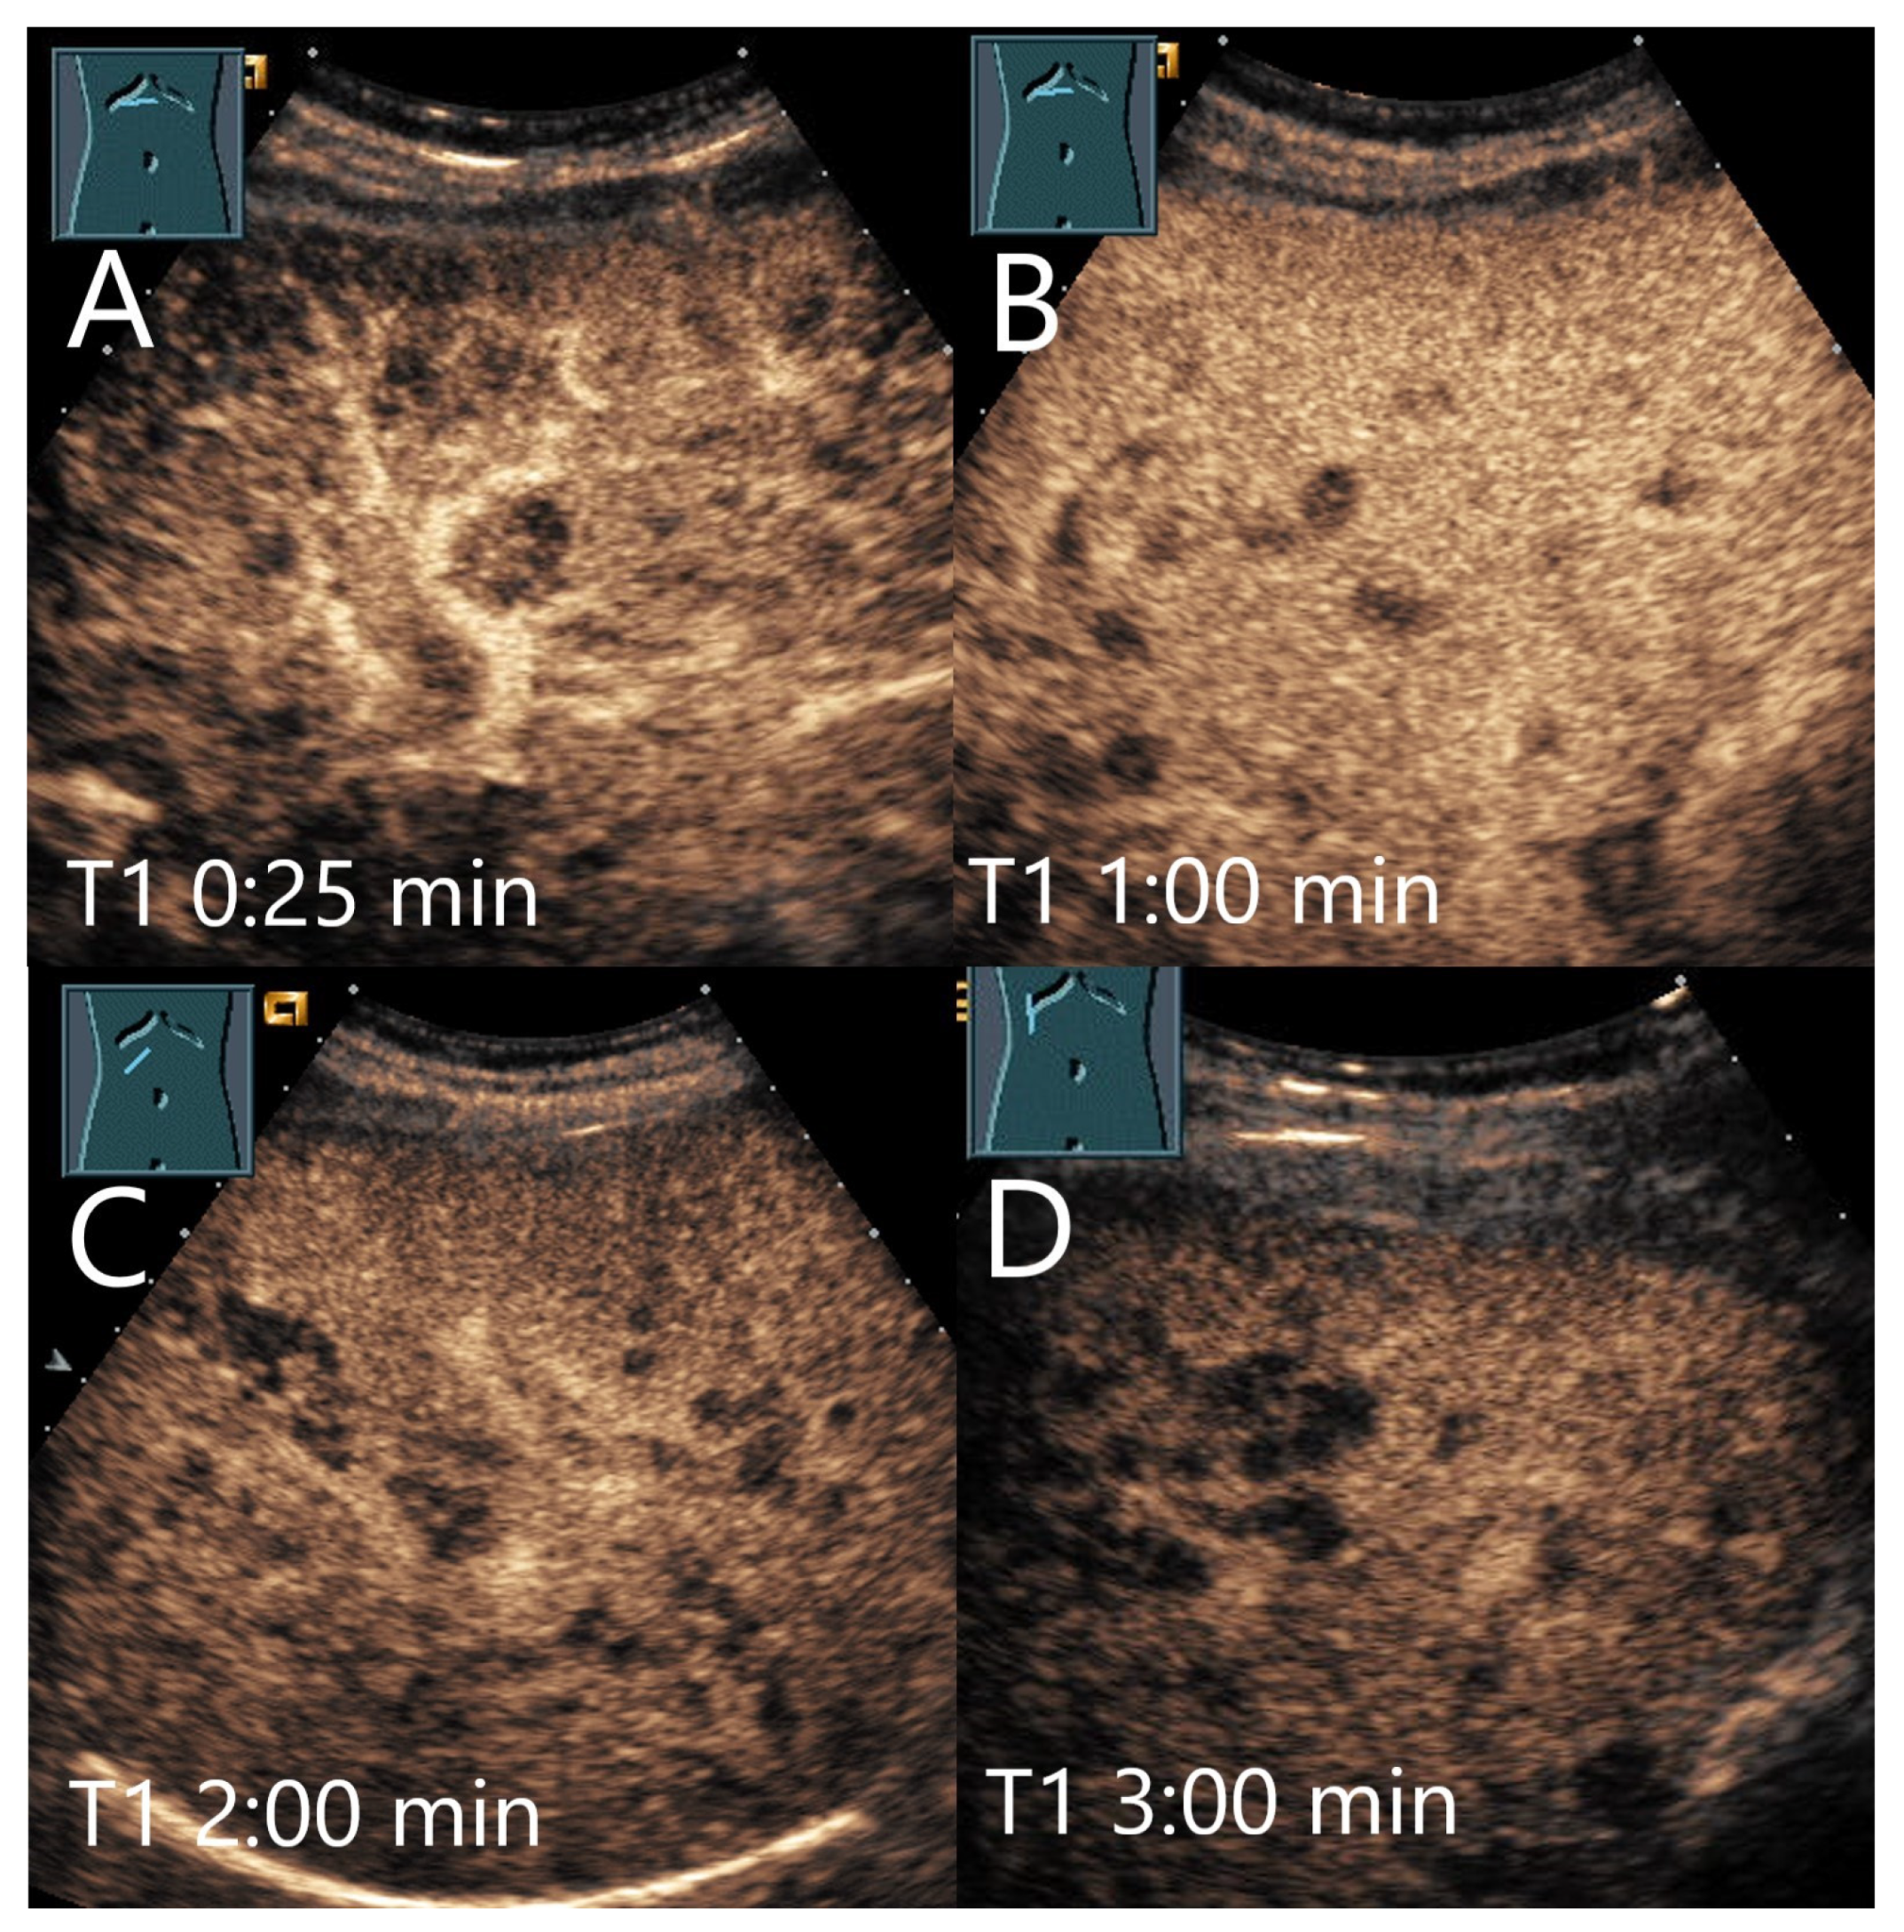

4.7. Peliosis

Peliosis hepatis (PH) is a benign condition that is histologically characterized by a proliferation of sinusoidal hepatic capillaries with blood-filled cystic cavities of varying size and irregular shape. Hepatic peliosis is usually asymptomatic. However, spontaneous bleeding may occur [141,142]. Post sinusoidal obstruction is suspected as a possible mechanism [143,144]. An altered venous outflow tract is discussed as the cause. However, the cause is often unclear. Chronic wasting diseases are frequently associated with peliosis, as are various Bartonella species. Bartonella henselae and Bartonella quintana cause bacillary peliosis in patients with AIDS [145,146]. In 2632 patients with newly diagnosed liver lesions and history of colorectal carcinoma, 9 (0.3%) had peliosis hepatis [147].

Hepatic peliosis is often an arterial hyperenhanced lesion that shows a washout in the PVP or LP on CEUS. A biopsy of these lesions is associated with a high risk of bleeding [148]. In a study of 24 patients, the hepatic peliosis lesions were mostly solitary, but also multiple. In B-mode US, the lesions appeared heterogeneously hypoechoic with well-defined margins but irregular shapes. On CEUS, 83% of the lesions showed a slight heterogeneous hyperenhancement in the AP, 12.5% a centrifugal hyperenhancement, and 16.7% an isoenhancement. Moreover, 87.5% of the lesions developed a slight washout with hypoenhancement in the PVP after 60 s and LP [141]. Further case reports reported hypoenhancement [149] or central hypoenhancement in the LP [150,151].

In another case report, an arterial homogeneous hyperenhancement was described, followed by an early progressive washout from 40 s [143]. The authors compared this appearance on CEUS with that of liver metastases or cholangiocellular carcinoma [143]. However, the washout does not appear to be obligatory. In another case with histologic confirmation of peliosis, the lesion showed central enhancement in the early AP with centrifugal spread and homogeneous enhancement in the LP [152].

In the study by Dong et al. [141], the typical histopathological features of parenchymal peliosis in the majority of patients were the presence of localized irregular sinusoids forming blood-filled spaces in the liver parenchyma, with thinning of the hepatic cell strands and the reticulin fiber network. In patients with the phlebectatic variant of peliosis, the presence of an endothelial lining along the blood-filled spaces caused by aneurysmal dilatation of the central vein was observed. In 28% of patients, the lining was secured by liver surgery. In all others, a needle biopsy was performed, with no major complications [141].

Ultimately, the final diagnosis of hepatic peliosis can usually only be confirmed histopathologically. Typical features are dilated sinusoidal spaces and hemorrhagic dilated spaces within the liver parenchyma, but this requires adequate tissue sampling. This may not be feasible in dilated sinusoidal spaces. In addition, a high risk of bleeding should always be taken into consideration with hepatic peliosis. However, the aspirates could also be examined for Bartonella species (Figure 19).

Figure 19.

Peliosis hepatis. Female patient. Hypoechoic lesion of 40 × 28 mm in a mildly steatotic liver (A). The CEUS shows arterial hyperenhancement after 25 s (B) with mild predominantly central hypoenhancement after 1 min (C) and 5 min (D). Histological confirmation was performed by US-guided biopsy. The adjacent small hypoechoic lesion (A) is isoenhanced in the CEUS in all phases.